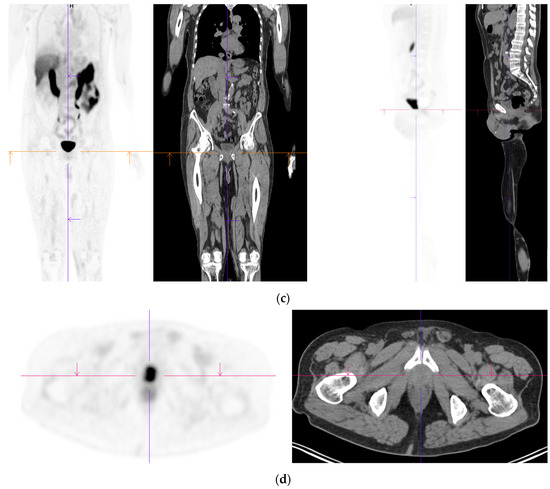

Figure 2.

Primary staging. 70 yr old M; PSA 42; Gleason 4 + 5 = 9; MR scan—PIRADS 6 at right apex; PIRADS 4 at left midzone. PSMA PET-CT: 68Ga-PSMA - 216 MBq; uptake 48 min; BMI = 30.5; Wt 83 Kg. (a): Coronal images—focal uptake midline apex anterior SUV = 26.1 with smaller focus SUV-5.4 right midzone; bulky disease in abdominal nodes; metastasis left humerus; left para-aortic node in thorax; bony metastasis left side of S1. (b,c): enlarged coronal and transaxial images of left common iliac/para-aortic nodal disease and uptake in apex of gland; transaxial images—node measures 14 mm SUV = 40.1; X-hairs show location. (d,e): enlarged coronal and transaxial images of right pelvic nodal that measures 1.4 mm SUV = 5.1; uptake in right midzone and apex as well as disease in left midzone of gland; X-hairs show location. (f,g): enlarged coronal images of para-aortic/para-oesophageal nodal disease in mediastinum; node measures 5.5 mm, SUV = 17.2; X-hairs show location.